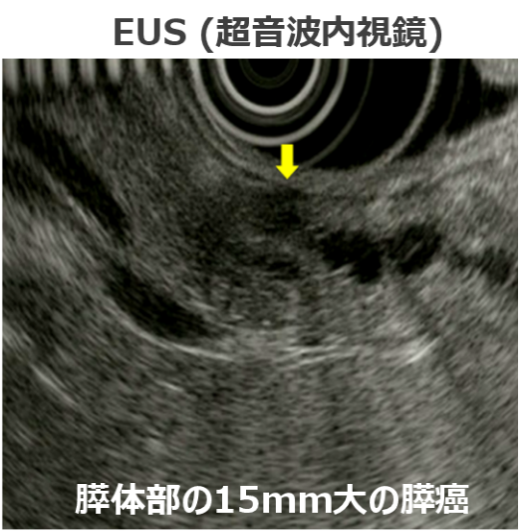

膵癌の診断にあたっては従来の検査法である体外式超音波、造影CT、MRI(MRCP)に加えて、超音波内視鏡(EUS)が非常に有用な検査法です。 特に20mm以下の小膵癌に対する感度はCTで40-67%、MRIで33%、EUSで90-100%と報告されています。EUSは外来でも検査可能であり、特に小膵癌の診断にEUSは必要不可欠な検査法です。

当院では膵癌に対する詳細なEUS診断が可能です。上記のような膵癌のリスクファクターを有する方は消化器センターまでご相談ください。